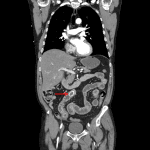

- 2.3 cm peripherally calcified structure likely representing a gallstone in the mid small bowel with upstream small bowel dilation, mural thickening, and submucosal edema

- Distally, the small bowel and colon are nondistended

- Gallbladder is collapsed with wall thickening, intraluminal gas, and demonstration of a fistulous connection to the adjacent duodenum

- Trace pneumobilia

- Inflammatory fat stranding about the above described loops of small bowel as well as surrounding the gallbladder

- Gallstone ileus

Findings are consistent with gallstone ileus. A 2.3 cm peripherally-calcified gallstone is identified in the mid small bowel with associated upstream small bowel dilation and inflammatory changes. Superimposed ischemia is not excluded, though there is no convincing pneumatosis or portal venous gas.

Decompressed gallbladder with associated inflammatory changes and demonstration of a cholecystoduodenal fistula.